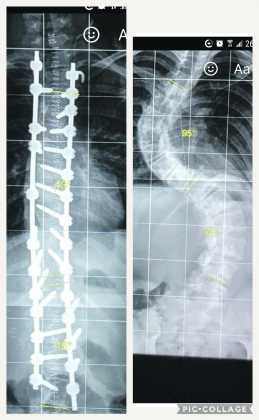

SHE has two titanium rods keeping her spine straight and twenty-seven screws holding them in place but the most steely thing about Limerick teenager Megan Halvey-Ryan is her determination.

Megan became the focus of media attention after an RTÉ television Prime Time special on hospital waiting lists revealed how her young life had been destroyed by scoliosis (curvature of the spine) as she waited years for an operation.

After a successful operation at the hands of surgeon Pat Kiely in Crumlin Hospital, Megan slowly got her life back and did the previously unthinkable last Sunday when she held a birthday party in a Chinese restaurant and invited her friends to the celebration.